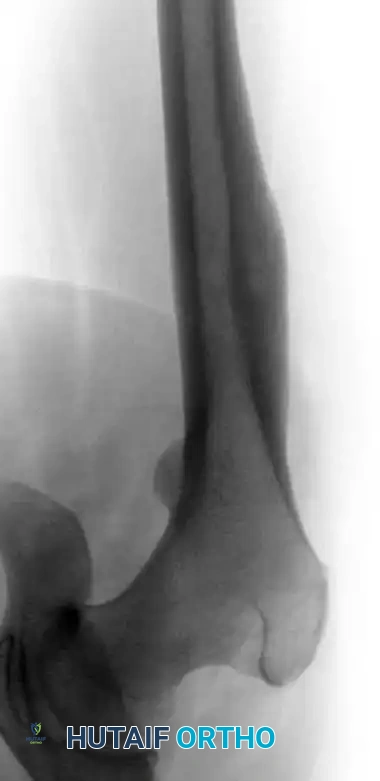

Lateral radiograph demonstrating an osteoid osteoma in the lateral cortex of the femoral diaphysis of a 16-year-old boy.

Standard orthogonal radiographs are often sufficient to establish the diagnosis, particularly in diaphyseal cortical lesions. The classic appearance is a small, radiolucent central nidus surrounded by a massive, thick rim of reactive sclerotic bone.

Plain Radiographs:

Imaging studies are usually definitive, and a biopsy is rarely required to confirm the diagnosis prior to definitive treatment. The diagnostic criteria hinge on identifying the central nidus, which by definition is less than 1.5 cm in diameter. Lesions identical in histology but larger than 1.5 cm are classified as osteoblastomas.